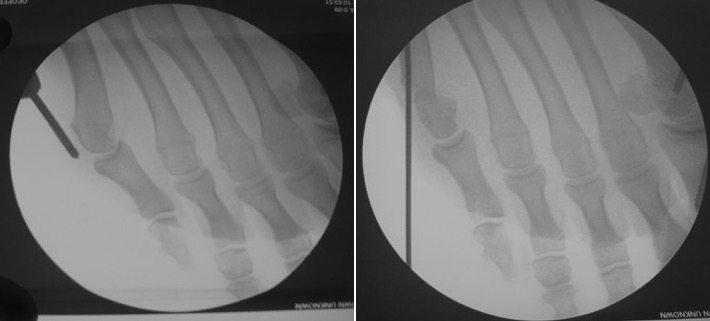

Technically, a motorized burr is introduced under the skin in contact with the bone, under the control of peroperative radiography (fluoroscopy). The burr’s rotation makes the bone cut, which allows to move the 5th metatarsal’s head“back inside the foot”.

The head’s fixation in its new location is assured with a metallic pin that does not hinder the immediate walking. It’s withdrawn during the consultation at 3 weeks, without any pain.